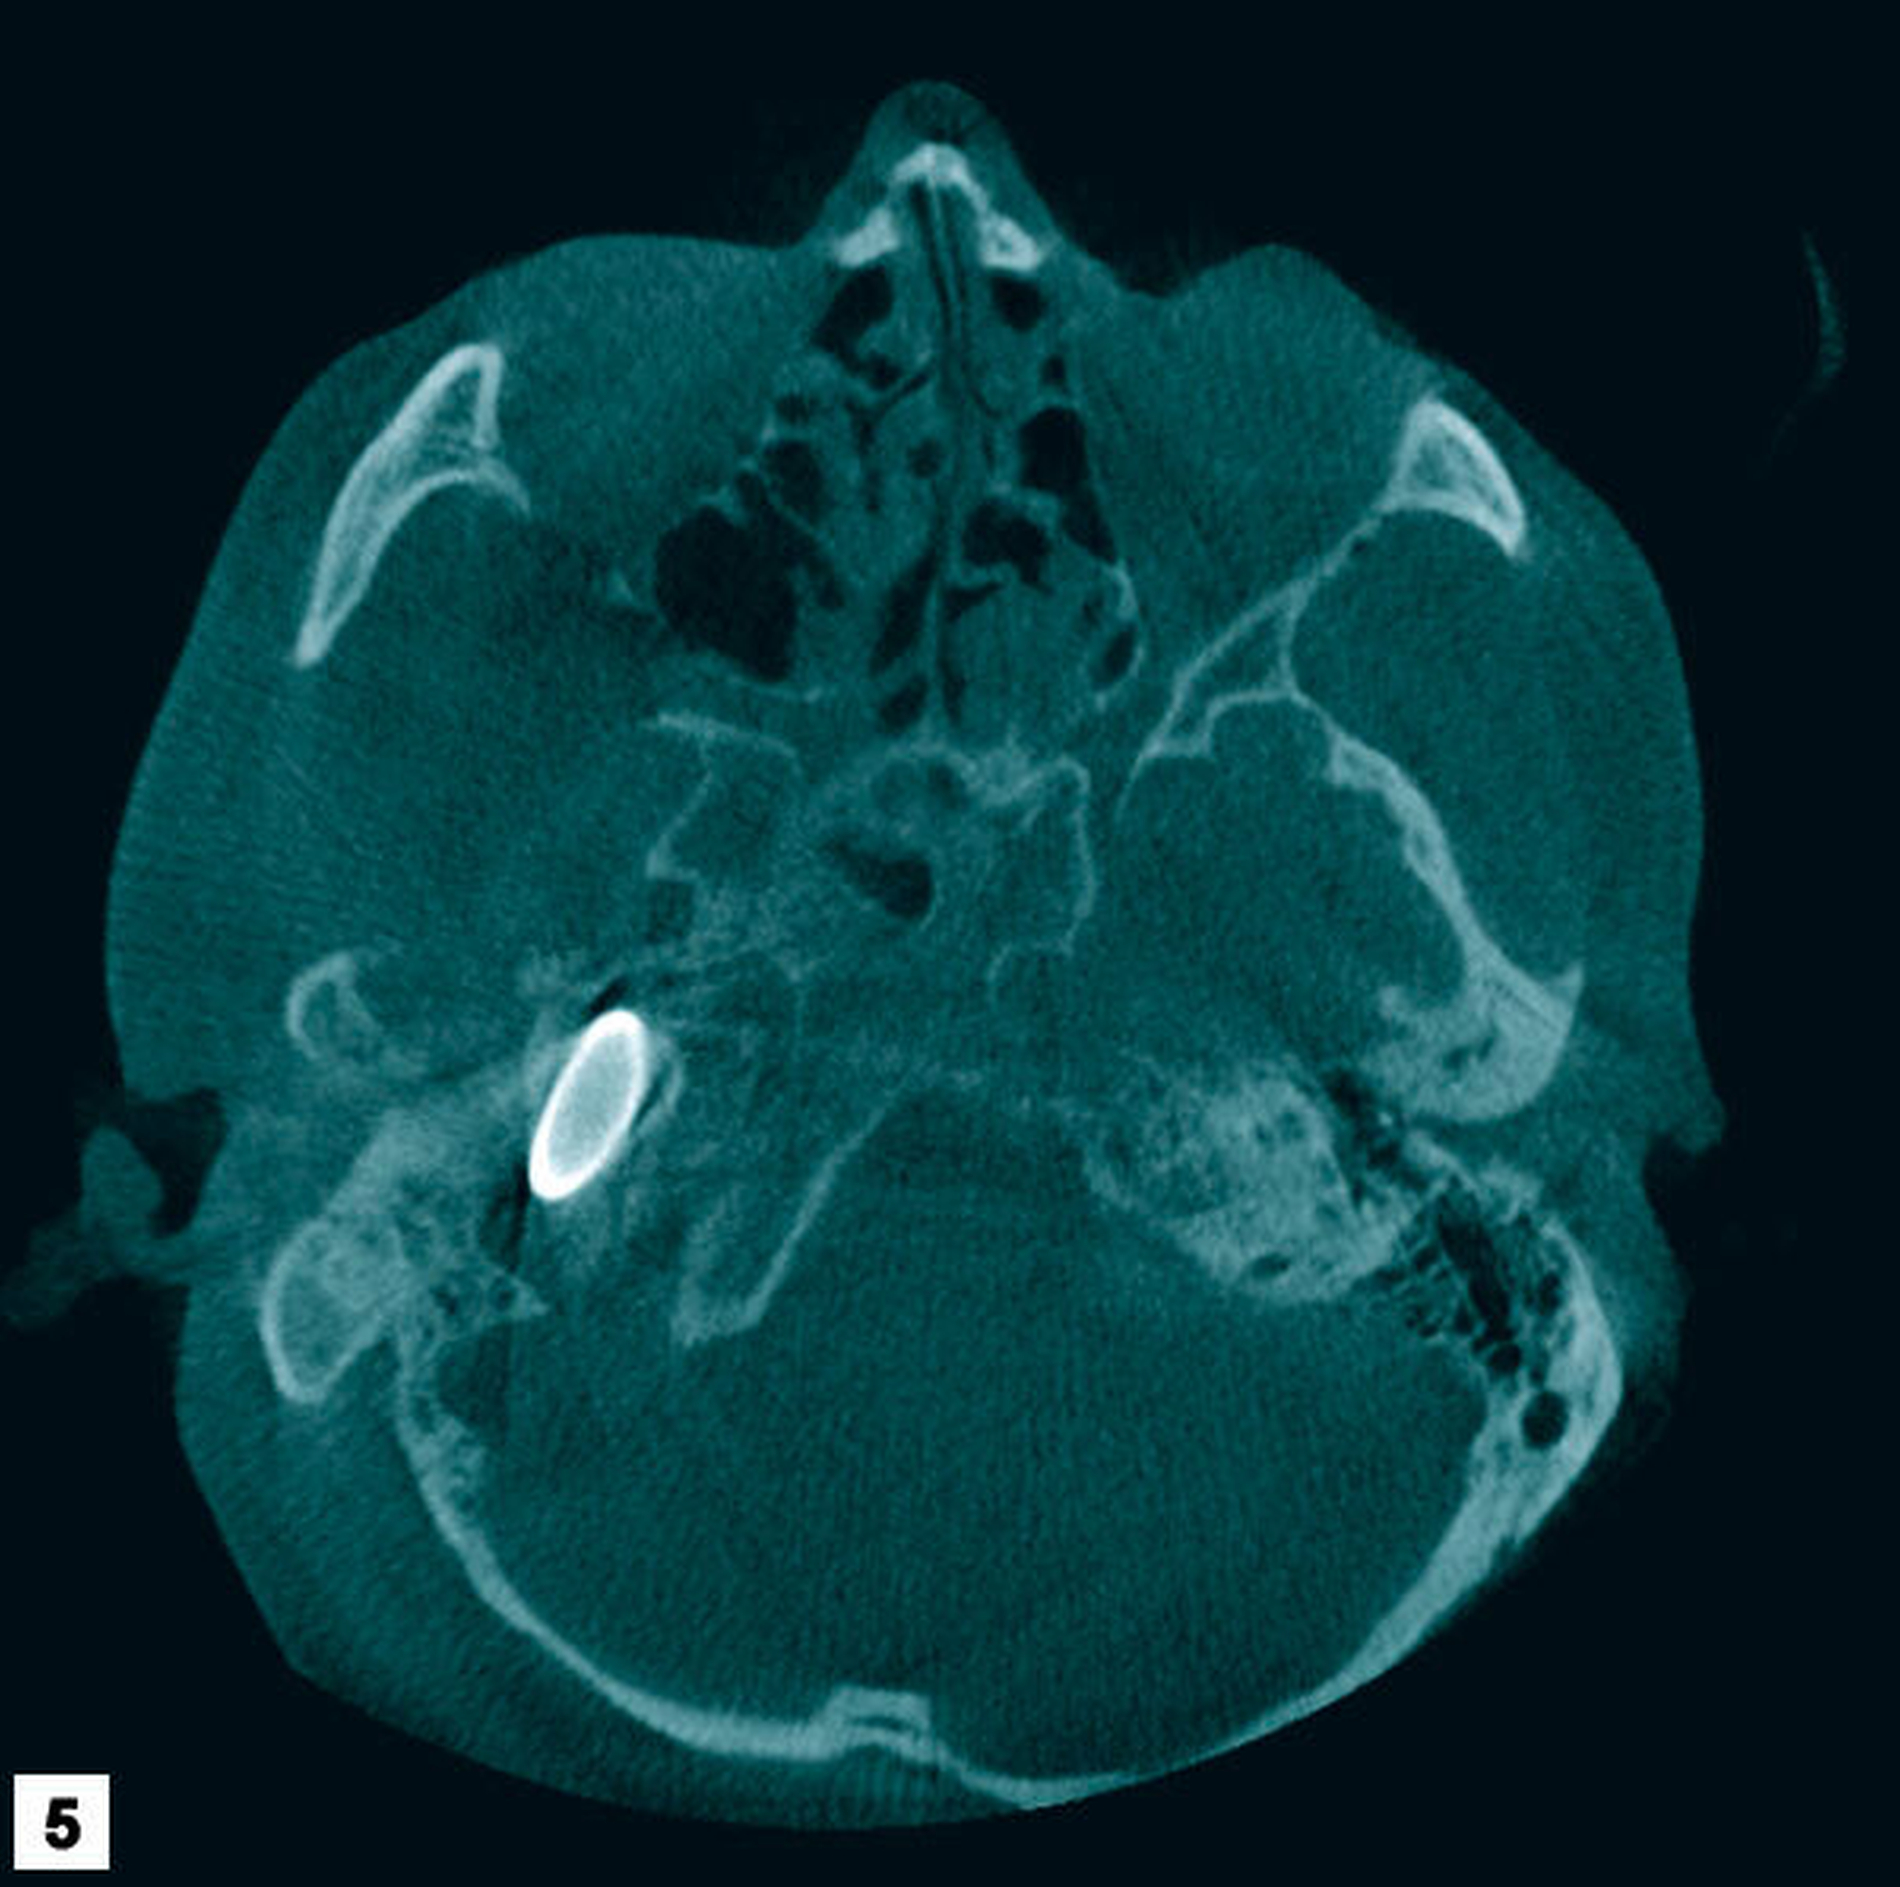

Zur weiteren Lokalisation in der dritten Ebene wurde eine Digitale Volumentomografie veranlasst. Diese Bilder zeigten neben einer großen Osteolyse apikal des Zahns 37 und deutlicher Schleimhautschwellung im Bereich der Sinus maxillares und ethmoidales einen metalldichten Fremdkörper im Bereich der Schädelbasis mit einer Ausdehnung von circa 7 mm x 38 mm mit einer projektiltypischen Form (Abbildungen 4 bis 6). Die Recherche lässt vermuten, dass dieses Projektil als Munition für ein Automat Kalaschnikow 47 Sturmgewehr (AK 47, wahre Größe der Kurzpatrone M 43 = 7,62 mm x 39 mm) passt.